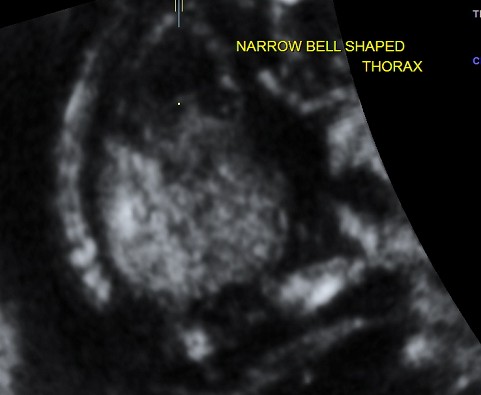

narrow , bell shaped chest , suggestive of pulmonary hypoplasia